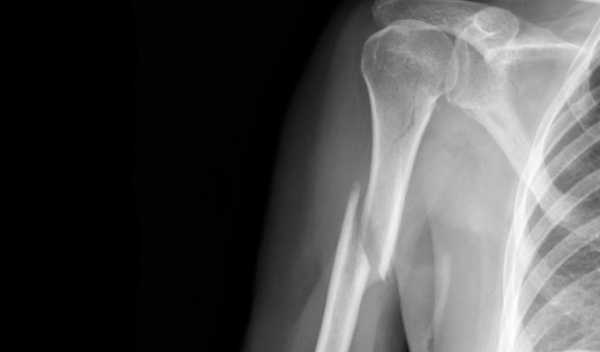

Современные методы диагностики перелома руки со смещением позволяют достоверно определить особенность перелома даже при размытой клинической картине. Осмотр пациента и рентгенографические снимки в разных проекциях дают информацию о характере излома, степени смещения, состоянии головки плеча и т. д.

Окончательный диагноз ставят только после проведения рентгенологического исследования. На снимке будет видно, на каком уровне сломана плечевая кость, в какую сторону произошло смещение.

Следующим шагом является рентгеноскопия травмированной конечности. При недостаточности этого метода, применяется магниторезонансная томография либо ультразвуковое обследование. Для полной картины понимания происшедшей травматизации и точности диагностирования пострадавшим сдаются анализы.

Исследование установит степень повреждения костной ткани.Закрытый перелом плеча диагностирует травматолог или хирург-ортопед. Врач выясняет обстоятельства травмирования, проводит визуальный осмотр, определяя степень двигательных нарушений и особенности симптомов, характерных для некоторых видов переломов, и направляет на рентгенографию. Процедура показывает присутствие или отсутствие смещения, сломан ли малый наружный мыщелок или надмыщелок плечевой кости, метаэпифиз лучевой косточки, состояние нервов, сосудов, связок и мышц. Для получения детальной клинической картины рекомендуется пройти:

Диагностика

По прибытии в больницу, врач проводит осмотр больного для точного определения вида и типа перелома, проводится рентгенография. Снимки делаются в двух проекциях, для более точной медицинской картины повреждения. При необходимости также делают УЗИ поврежденного участка или МРТ. Таким образом, повреждения мышц, сосудов или нервов определяются вовремя, и назначается соответствующий курс лечения. Осмотр врачом включает следующие действия:

Окончательный диагноз врач может установить, только изучив рентгеновские снимки. На них можно определить расположение осколков и смещение участков кости.